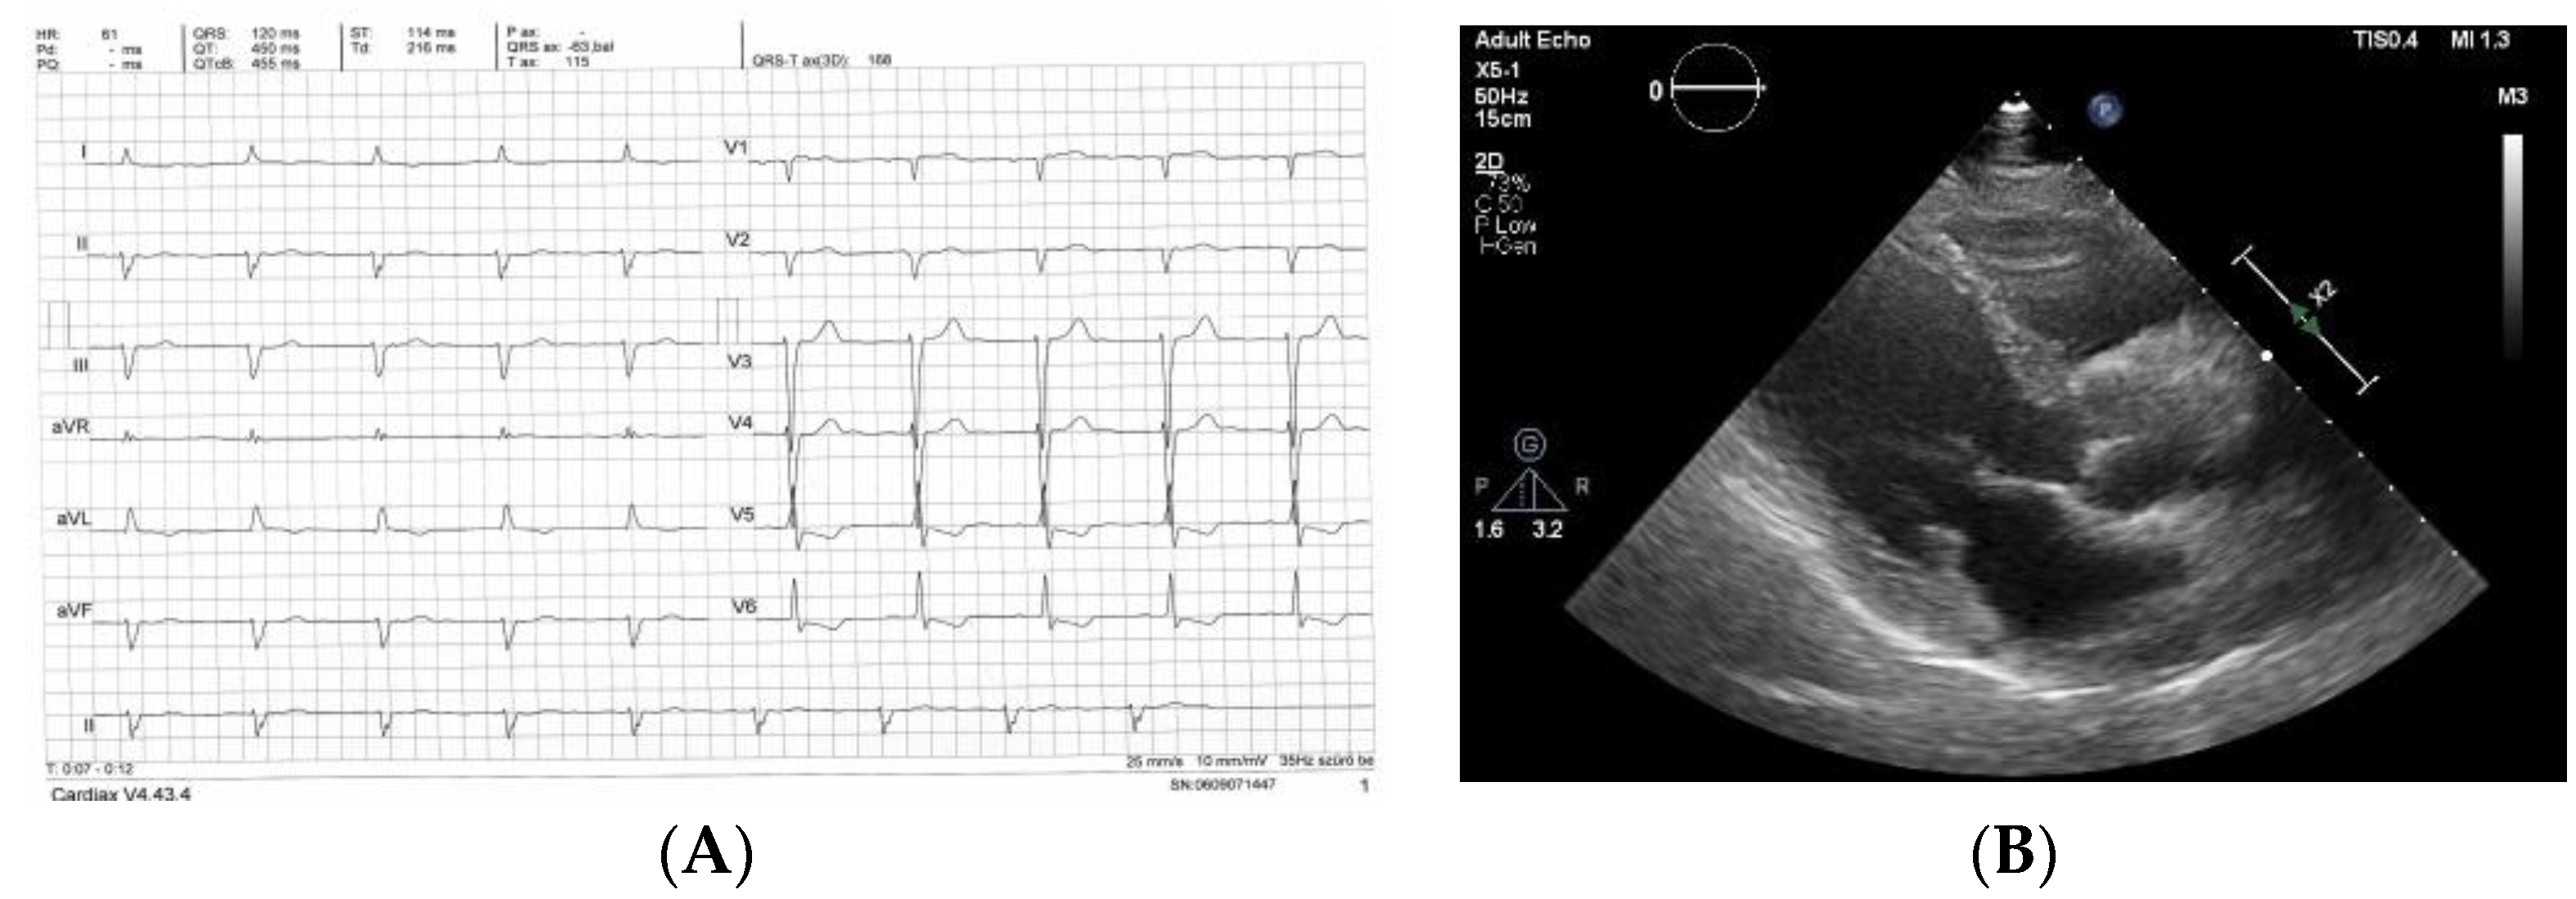

| Pt | Age at Diagnosis (Years) Sex of Patient | Left Ventricular Septal/Inferior/Average Wall Thickness (mm) EDV (mm)/ EF Measured with Echocardiography | E/e’ | Stage of Heart Failure According to NYHA at the Time of Diagnosis | NTproBNP (pg/mL) | Troponin T (ng/L) | GFR (mL/min/ 1.73 m2) | Organ from where the Biopsy Proved AL Amyloidosis | Result of CMR | Known PCD Before the Diagnosis of CA | Complaint, Symptom that Led to the Diagnosis of CA/Other Clinically Significant Organ Involvement |

|---|---|---|---|---|---|---|---|---|---|---|---|

| 1 | 65 male | 10/10/10 | 33.5 | IV | 6492 | 50 | 23 | rectum | typical for CA | No | heart failure/ polyneuropathy |

| 54/22 | |||||||||||

| 2 | 59 male | 10/10/10 43/56 | 8.95 | II | 2106 | 55 | 108 | heart | typical for CA | Yes | heart failure/ polyneuropathy |

| 3 | 52 male | 11/11/11 | 16 | III | 1537 | 42 | 80 | heart | typical for CA | No | heart failure/CTS, polyneuropathy |

| 42/63 | |||||||||||

| 4 | 75 female | 12/11/11.5 43/35 | 18.6 | III | 4311 | 96 | 112 | skin of eyelid | NP | No | heart failure/- |

| 5 | 59 female | 10/10/10 36/63 | 14 | I | 1436 | 69 | 26 | kidney | NP | Yes | screening for CA/ nephrotic syndrome |

| 6 | 72 female | 11/12/11.5 41/40 | 35.8 | IV | 6925 | 50 | 85 | abdominal fat | typical for CA | No | heart failure |

| 7 | 56 male | 9/9/9 42/53 | 13.9 | II | 573 | 32.9 | 113 | skin of eyelid, capsular ligament | LGE in atrial walls | Yes | screening for CA/ joint pain/ CTS |

| 8 | 58 female | 10/10/10 36/60 | 8.9 | I | 486 | 10 | 51 | kidney | not typical for CA | Yes | screening for CA/ polyneuropathy/ nephrotic syndrome |

| 9 | 82 female | 11/11/11 51/60 | 15.6 | II | 1717 | 8 | 51 | abdominal fat | not typical for CA | Yes | heart failure |